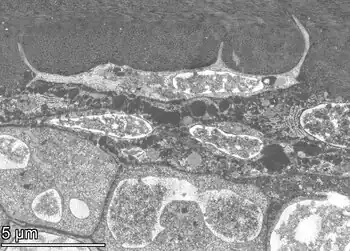

An osteocyte, an oblate-shaped type of bone cell with dendritic processes, is the most commonly found cell in mature bone. It can live as long as the organism itself.[1] The adult human body has about 42 billion of them.[2] Osteocytes do not divide and have an average half life of 25 years. They are derived from osteoprogenitor cells, some of which differentiate into active osteoblasts (which may further differentiate to osteocytes).[1] Osteoblasts/osteocytes develop in mesenchyme.

In mature bones, osteocytes and their processes reside inside spaces called lacunae (Latin for a pit) and canaliculi, respectively.[1] Osteocytes are simply osteoblasts trapped in the matrix that they secrete. They are networked to each other via long cytoplasmic extensions that occupy tiny canals called canaliculi, which are used for exchange of nutrients and waste through gap junctions.

Osteocytes have a stellate shape, approximately 7 micrometers deep and wide by 15 micrometers in length.[3] The cell body varies in size from 5–20 micrometers in diameter and contain 40–60 cell processes per cell,[4] with a cell to cell distance between 20–30 micrometers.[3] A mature osteocyte contains a single nucleus that is located toward the vascular side and has one or two nucleoli and a membrane.[5] The cell also exhibits a reduced size endoplasmic reticulum, Golgi apparatus and mitochondria, and cell processes that radiate largely towards the bone surfaces in circumferential lamellae, or towards a haversian canal and outer cement line typical of osteons in concentric lamellar bone.[5] Osteocytes form an extensive lacunocanalicular network within the mineralized collagen type I matrix, with cell bodies residing within lacunae, and cell/dendritic processes within channels called canaliculi.[6]